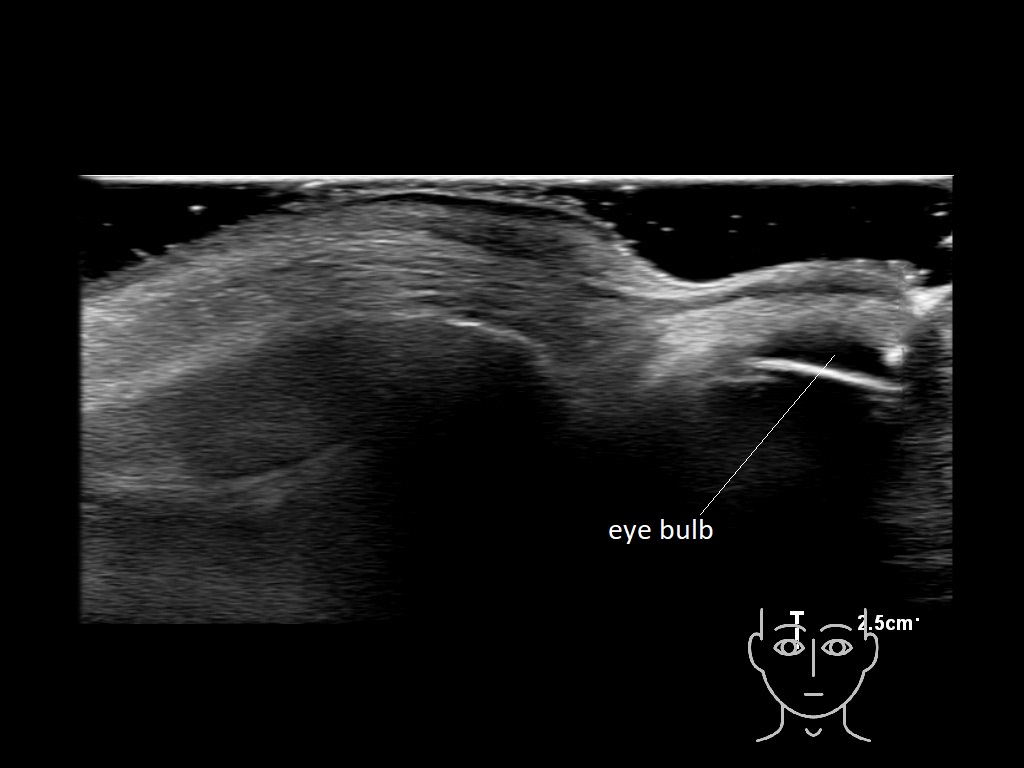

In this section you will learn more about the different layers of the face with the use of ultrasound. When you click on the secondary ultrasound image, you will see the different structures as an overlay. This will help to train yourself to recognize the different layers of the face.

Study the first image to recognize the different layers. If you are sure about the layers, swipe to the second image to view the answer (if applicable).